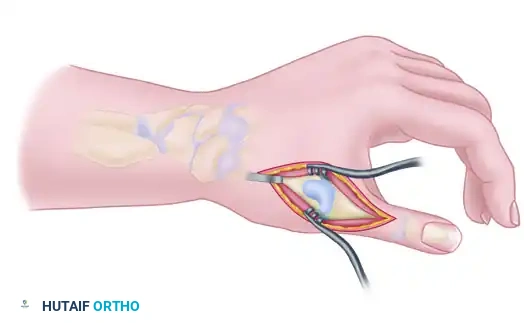

Surgical Management of Volar Synovitis

- Exposure: An extended carpal tunnel incision is utilized, crossing the wrist crease obliquely to avoid contracture.

- Decompression: The transverse carpal ligament is completely released to decompress the median nerve.

- Tenosynovectomy: A meticulous, tendon-by-tendon synovectomy is performed. The surgeon must inspect the floor of the carpal tunnel (the volar radiocarpal ligaments).

- Bony Debridement: Any protruding osteophytes from the radius or scaphoid must be aggressively rongeured flat, and the defect covered with a local capsular flap to prevent recurrent tendon abrasion.